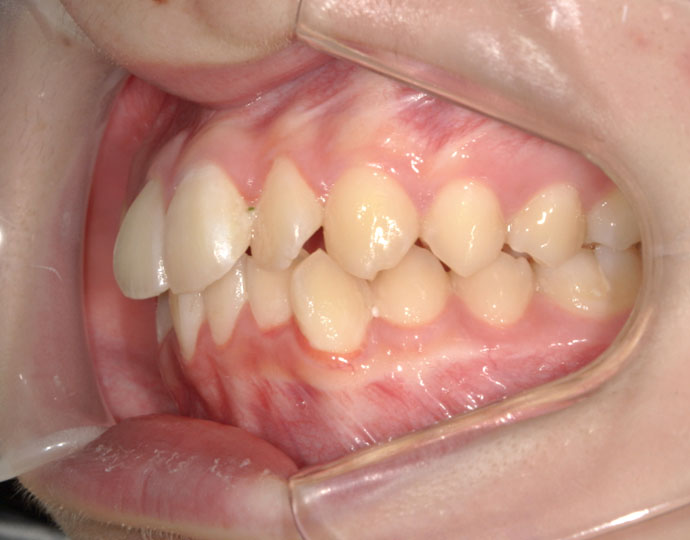

治療後

| 患者様 | 女性 18歳 |

| 主訴 | 歯並びを綺麗にしたい。 |

| 診断 | 叢生歯列不正咬合 |

| 治療方針 | 上下顎左右第一小臼歯の抜歯(計4歯) |

| 治療に使用した装置 | セルフライゲーションブラケット(インタラクティブタイプ) |

| 治療期間 | 2年2カ月 |

| 治療回数 | 24回 |

| 治療費(自費診療) | 847,000円(税込み) |